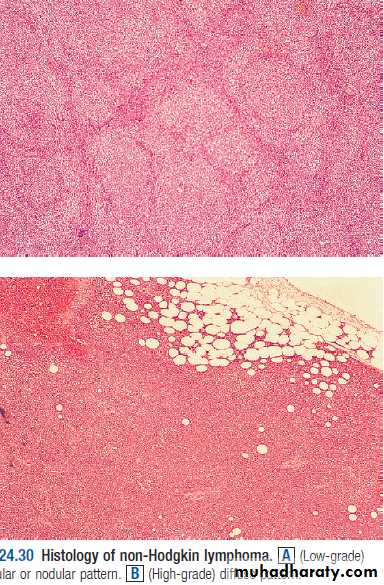

Most present as tumor Involving lymph nodes or otherlymphoid organs such as the spleen. But extra nodalpresentation may seen.1. Hodgkin’s Lymphoma.2.Non - Hodkin’s Lymphoma; Non-Hodgkin lymphomas areclassified as low- or high-grade tumours on the basis of theirproliferation rate.High-grade tumours divide rapidly, are typically present for amatter of weeks before diagnosis, and may be life-threatening.• Low-grade tumours divide slowly, may be present for manymonths before diagnosis, and typically behave in an indolentfashion.

Non-Hodgkin lymphomaNon-Hodgkin lymphoma (NHL) represents a monoclonalproliferation of lymphoid cells of B cell (70%) or T cell (30%)origin.working formulation for lymphoma classification• Low grade :• diffuse small lymphocytic.• follicular small cleaved cell.• follicular mixed small and large cell.• Intermediate grade :• diffuse small cleaved cell.• diffuse small and large cell.• diffuse large cell lymphoma.• follicular large cell lymphoma.• High grade :• immunoblastic lymphoma.• small non cleaved cell (Burkitt-type).• lymphoblastic lymphoma.